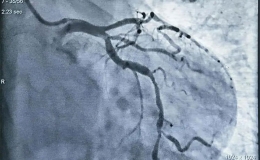

淮南东方医院集团心血管内科医疗中心完成首例OCT指导下冠脉支架植入术

东方医院集团心内科医疗中心近期,淮南东方医院集团心血管内科医疗中心完成了首例冠脉光学相干断层成像技术(OCT)指导下的冠状动脉支架植入术。标志着我院冠脉介入诊疗迈入“精准医疗”......

来源:心内科浏览:195 次发布时间:2023-08-01 14:30:17 -